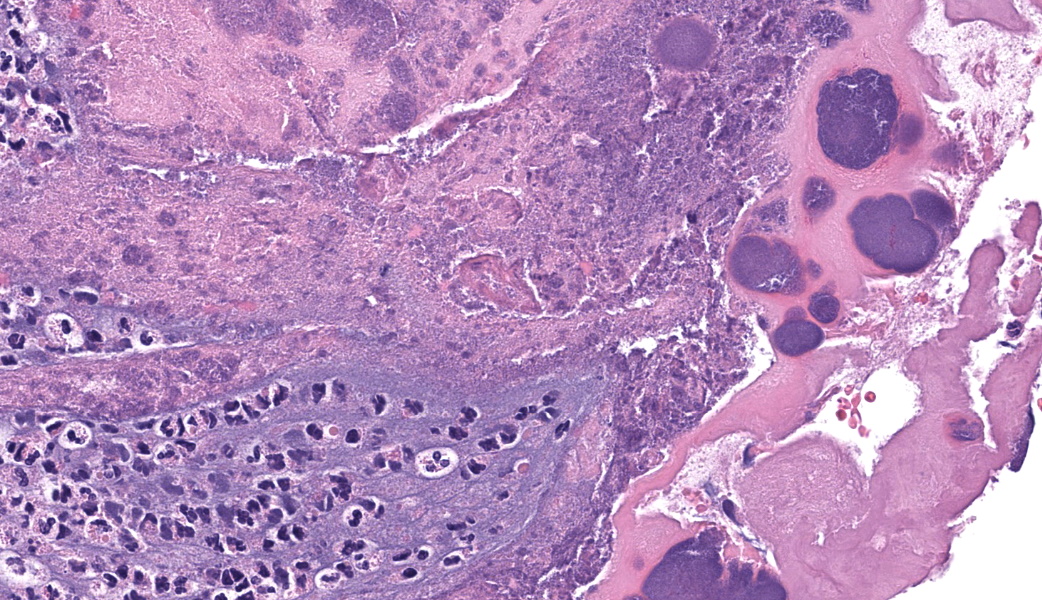

Representative sections of heart and lungs are examined.In the heart, the right atrioventricular valve is extensively overlain by large mats of fibrin, admixed with numerous degenerate and viable neutrophils and multiple coccobacilli bacterial colonies. The valvular stroma is diffusely expanded by moderate myxedema and there are moderate numbers of neutrophils and lesser numbers of hemosiderin-laden macrophages, plasma cells and lymphocytes scattered throughout the valvular stroma and expanding the endocardium of the adjacent papillary muscles. The epicardium and surrounding adipose tissue are mildly infiltrated by small numbers of neutrophils, lymphocytes, and plasma cells.

Heart, right atrioventricular valve: Marked, chronic, fibrinosuppurative valvular endocarditis with intralesional bacterial colonies; Mild, multifocal, suppurative epicarditisLungs: Marked, regional, suppurative, necrotizing embolic pneumonia with vascular thrombosis and intrathrombotic bacteria; Marked, regional, fibrinosuppurative pleuritis

1. Heart, right AV valve: Valvulitis, fibrinosuppurative, chronic, focally extensive, severe, with valvular remodeling and numerous colonies of coccobacilli.